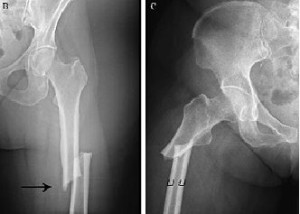

El efecto de la terapia con bisfosfonatos a largo plazo sobre la resistencia ósea trabecular y la densidad de microgrietas

Se halló reducción de la resistencia y un aumento de microgrietas en el hueso tratado con bifosfonatos. Bone Joint Res, 27 de octubre de 2017